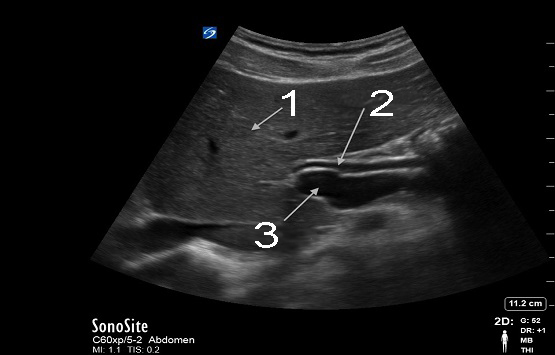

Gallbladder Common Bile Duct (CBD) Image

Liver

Common Bile Duct (CBD)

Portal Vein